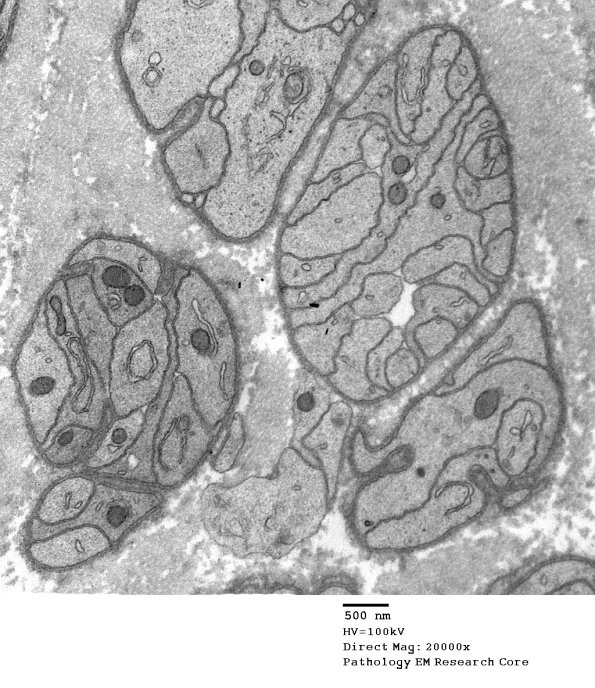

Schwann cells form bands of Büngner once axons degenerate. (electron micrographs)